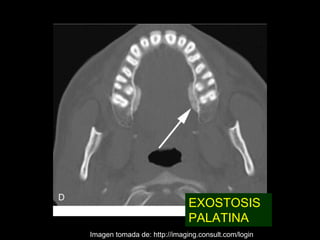

EXOSTOSIS

PALATINA

Imagen tomada de: http://imaging.consult.com/login

Exostosis CaracterísticasRadiográficas • Densidad: Radiopaca • Limites y Bordes: Limites definidos sin borde corticalizado • Tamaño: variable • Localización: Pueden ser bucales o linguales • Usualmente son simétricos bilaterales

EXOSTOSIS PALATINA Imagen tomada de: http://imaging.consult.com/login